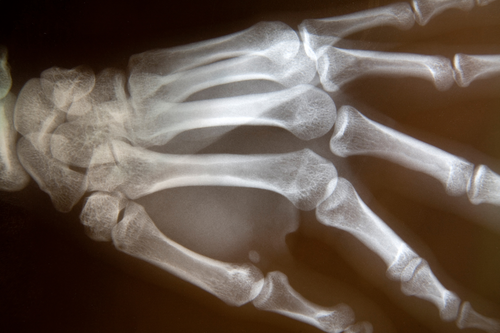

All of the above-mentioned fungal infections can cause fungal arthritis. Doctors test for arthritis using procedures such as x- rays and synovial (joint) fluid biopsies.